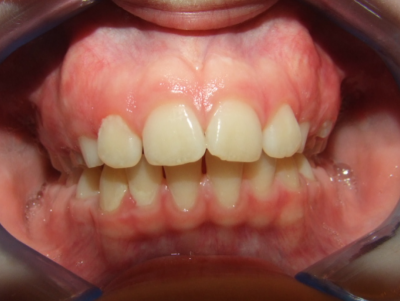

Leeftijd bij aanvang: 10 jaar

Bonded Hyrax + volledig vast onderkaak

Volledig vast bovenkaak + expander

Wrap + c-c bar onderkaak

Leeftijd bij afname: 12 jaar

Voor behandeling

Na behandeling